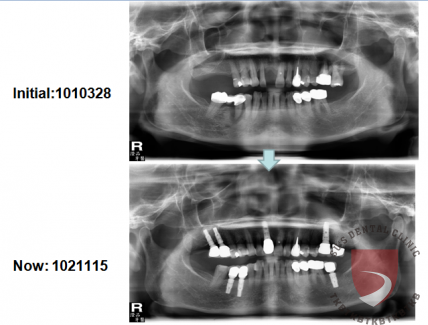

高蛀牙率合併牙周病 牙齒移位

牙周病造成多處缺牙